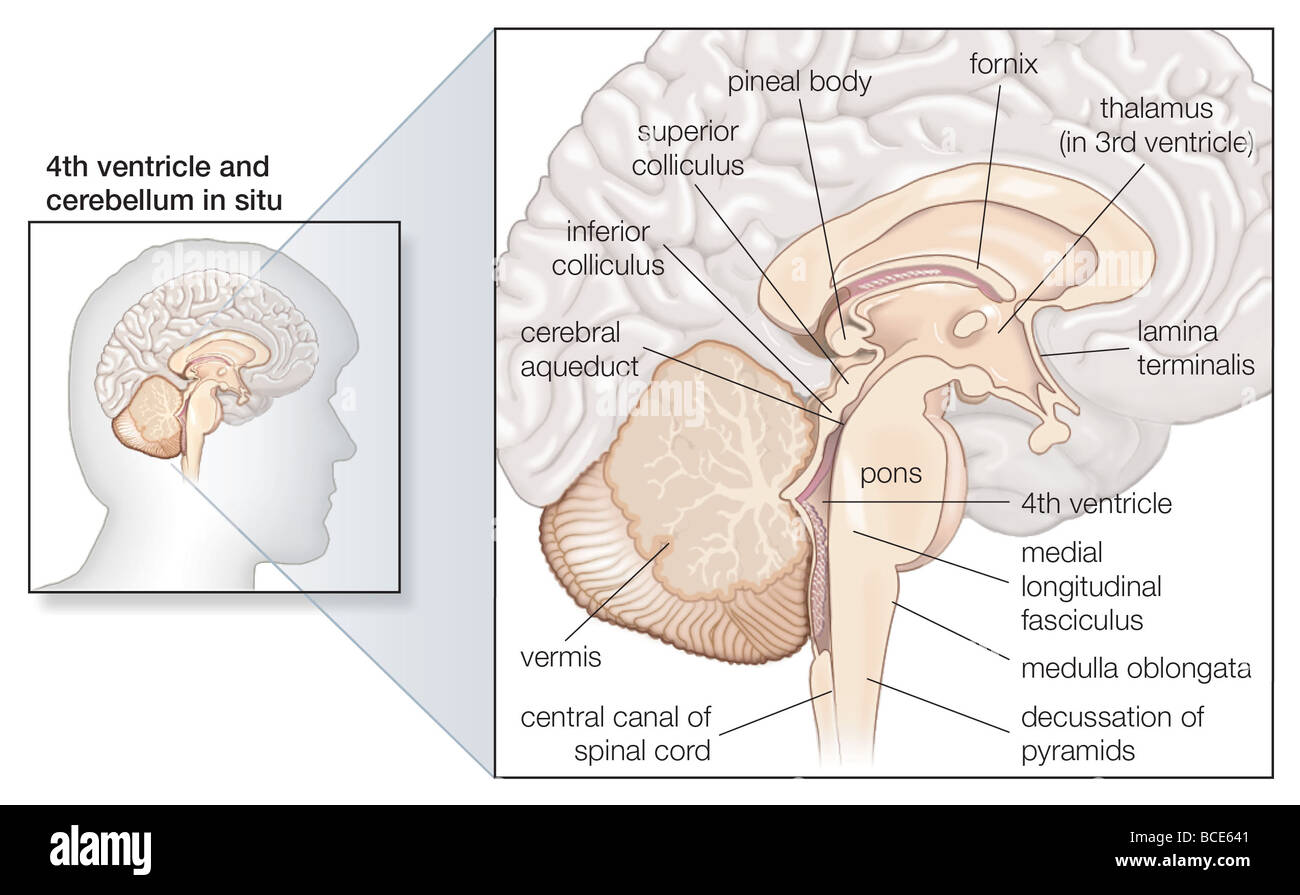

RMBCE641–Sagittale Abschnitt des menschlichen Gehirns, Darstellung von Strukturen der zerebralen Ventrikel, Kleinhirn und Hirnstamm.

RM2AWFNN9–Menschliche Anatomie, einschließlich Struktur und Entwicklung und praktische Überlegungen d in einem sagittalen mesialen Abschnitt (Abb. 910) wird jede dieser Teilungen als mit einem Teil des Systems der Kommunikation von Räumen verwandt angesehen, die als die dritten Ventrikel des Lateralands, der Aquädukt von Sylvius und der vierte Ventrikel die oben genannten Gehirnhemisphären ausdehnen. Durch den Hirnstamm und unter dem Kleinhirn bis zum zentralen Kanal des Rückenmarks. Da die lateralen Ventrikel zwei innumerieren, ist die Theirstellung im Zusammenhang mit den Gehirnhemisphären, in denen sie liegen, lateral zum m

RM2CDFE0C–. Elemente der physiologischen Psychologie; eine Abhandlung über die Aktivitäten und die Natur des Geistes, aus der physischen und experimentellen Gesichtspunkten. ide,die corpora quadrigemina. Die Kavität des Neuralrohres bleibt hier klein und bildet das Aquädukt, das den Viertmit dem dritten Ventrikel verbindet. Im Zwischenhirn dehnt sich das Aquädukt in den dritten Ventrikel aus; und hier wird wieder die dorsale Wand des Tubus zu einer breiten, dünnen Membran, die in den Ventrikel gefaltet und Blutgefäße mit sich trägt. Während die zerebralen Hemisphären ihr enormes Wachstum durchlaufen, dehnt sich die Kavität mit ihnen aus, andrema